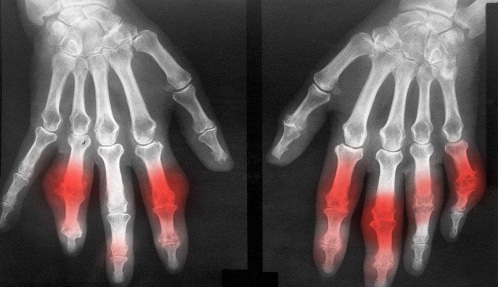

类风湿性关节炎是生活中较为普遍的疾病,其特征是手,足小关节的多关节、对称性、侵袭性关节炎症,所以当手指关节出现异常情况下,不可轻易忽视,好是到正规医院进行详细的检查,以便能够及时治疗。》》》点击此处,在线咨询云骨专家,如何治疗类风湿性关节炎

云南骨科医院介绍,手指类风湿性关节炎的治疗方法有很多种,具体介绍如下:

云骨专家提醒:手指类风湿性关节炎的治疗方法比较多,具体方式的选择需根据自身实际情况而定,需要注意的是患者如果早晨起床时发现手指关节僵硬,尤其是症状持续时间比较长的朋友,一定要注意,这可能是类风湿性关节炎的信号。》》》百看不如一诊,点击此处在线咨询